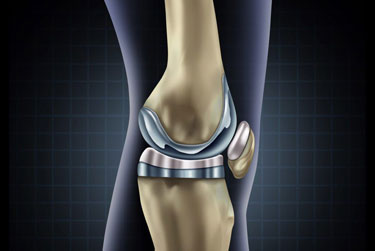

Dr Prateek Kumar is a highly qualified compassionate orthopaedic surgeon with over 15yrs of experience in field of Orthopaedic & Arthroplasty.He has received his medical education from renowned Institutions in India & has continuously updated his knowledge to stay at the forefront of medical advancement. Dr.Prateek Kumar is committed to providing the best possible care to his patients ensuring their comfort and well being throughout their treatment.